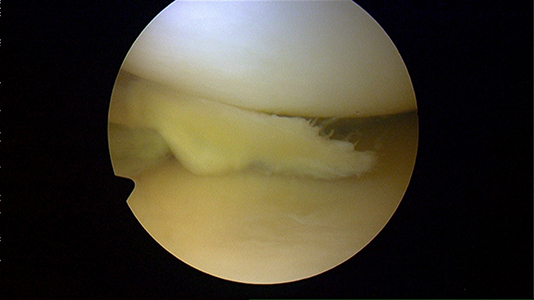

Fragment méniscal (ou « flap »)

Après régularisation

Le traitement consiste en la résection partielle du ménisque, soit sa partie instable responsable de la douleur.